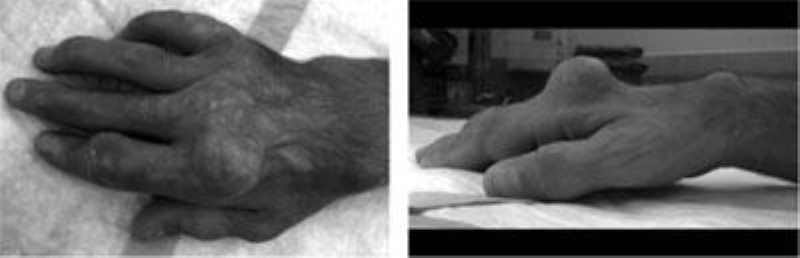

tophi in hand

Tophi in the hand, shown from above and the side.

(Reproduced from Fitzgerald BT, Setty A, Mudgal CS: Gout affecting the hand and wrist. J Am Acad Orthop Surg 2007:15:625-635.)

If uric acid levels remain high over a long period of time, deposits can develop around joints and tendons. These chalky deposits, called tophi, look like white toothpaste and create visible lumps under the skin.

Once gout reaches the chronic stage — which takes several years — joints may have permanent damage and deformity, and pain may be constant. When properly treated, most cases of gout will not progress to this disabling stage.